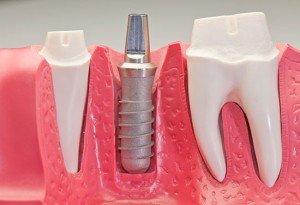

Una delle caratteristiche fondamentali della connessione implantoprotesica è l'affidabilità meccanica, che assieme alla precisione ha un impatto decisivo sulla qualità e sulla...

Il successo in implantologia a breve e lunga distanza è strettamente dipendente dalla qualitàe dalla quantitàossea. In aggiunta, il desiderio di raggiungere un'osteointegrazione...

Il successo implantare è determinato da numerosi fattori, fra questi la qualità ossea riveste un'importanza fondamentale. La densità ossea al sito di posizionamento determina...